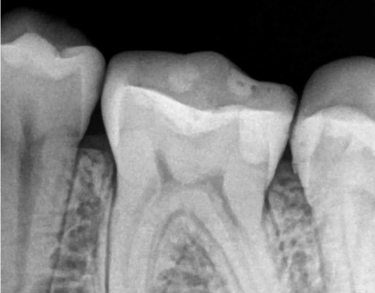

RTG punktowe to jedno z podstawowych badań radiologicznych w stomatologii, umożliwiające dokładną ocenę pojedynczego zęba oraz otaczających go struktur. Badanie pozwala wykryć próchnicę, ocenić stan korzeni, kanałów zębowych oraz tkanek okołowierzchołkowych.

W naszej pracowni RTG stomatologicznego w Gdyni wykonujemy zdjęcia punktowe, które stanowią niezastąpione wsparcie w leczeniu kanałowym, diagnostyce stanów zapalnych i urazów zębów. Badanie jest szybkie, bezpieczne i precyzyjne, zapewniając lekarzowi pełne informacje potrzebne do skutecznego planowania leczenia.